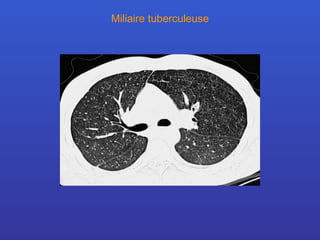

Miliaire tuberculeuse

Calcifications pulmonaires Analyse en fonction de leur aspect morphologique calcification diffuses d’aspect miliaire -  histoplasmose, hémosidérose, tbc calcifications nodulaires multiples -  parasitoses, silicose, varicelle ossifications de forme nodulaire -  calcifications valvulaires mitrale calcification nodulaire unique -  tuberculose, hématome calcifications au sein de nodules multiples - métastases chondrosarcome, ostéosarcome calcifications arciformes -  paroi d’une bulle, kyste hydatique